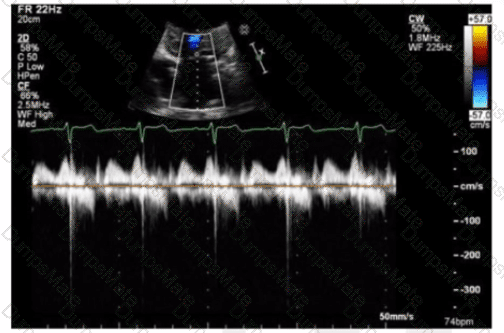

Which next step is appropriate after obtaining the Doppler signal in this image?

AE-Adult-Echocardiography Question 14

Options:

A.

Pulsed wave at various levels of the left ventricle to localize intracavitary gradient.

B.

Pulsed wave at the level of the mitral valve leaflet tips to assess for mitral stenosis

C.

Continuous wave through the left ventricle to localize intracavitary gradient

D.

Continuous wave through the mitral valve to assess for mitral stenosis